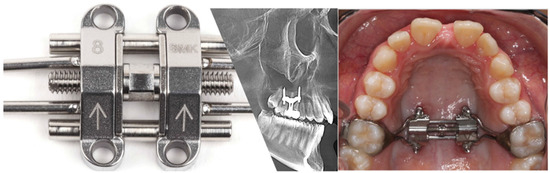

2.1. MSE Design and Activation Protocol